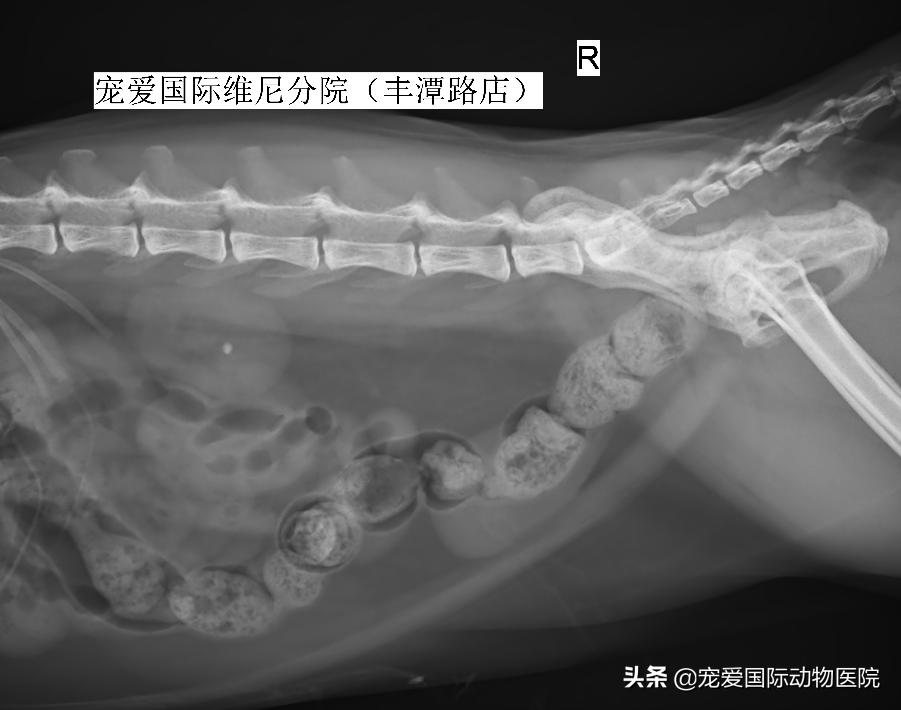

B超检测,见右侧肾盂扩张

内有一直径6MM结石

右侧肾结石,右侧输尿管堵塞

部分患宠肾结石可能会在数小时或数日自行排出,反复进行X光片检查可帮助追踪其过程。若结石引起输尿管阻塞、肾衰竭,或者结石造成输尿管严重损伤等,通常需借助外科手术手段,但因为猫的输尿管特别细,输尿管结石取出手术还需要特殊的放大设备等。